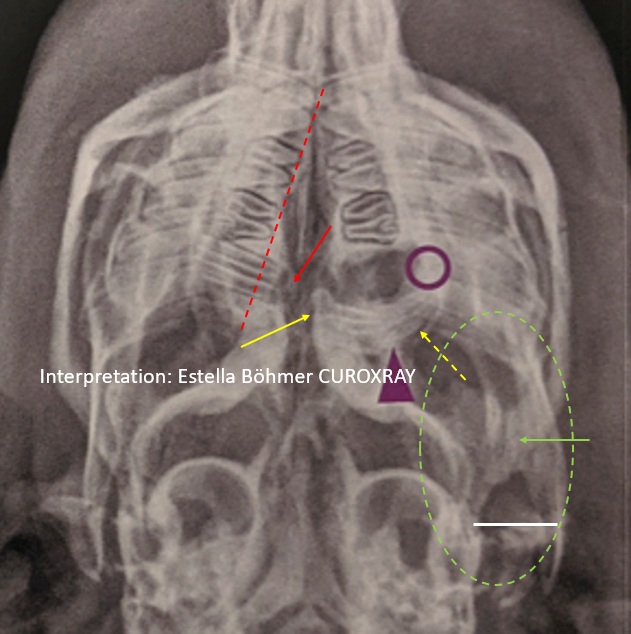

Punkt 6: zusätzlich erkennbare Patholgien finden keine Erwähnung

In der Bildbeschreibung werden lediglich die Zahnveränderungen und die Knochenlyse beschrieben, wobei der lila Kreis aber eigentlich nicht darauf hinweist. Nicht erwähnt werden die höchstgradige strukturelle Veränderung des betroffenen Backenzahnes (M3) bis in den apikalen Bereich hinein, einhergehend mit einer ausgeprägten apikalen Elongation (gelber Pfeil) sowie einer vor allem kaudal erkennbaren entzündlichen Zahnfacherweiterung (gelber gestrichelter Pfeil). Ebenso ignoriert werden die ausgeprägte apikale Elongation des M3 im rechten Oberkiefer (roter Pfeil und rote gestrichelte Linie) und eine vermutlich vorliegende Veränderung des linken Kiefergelenkbereiches (grüner gestrichelter Kreis). Der kaudale Unterkieferast liegt linksseitig viel weiter entfernt von der lateralen Wand der Bulla tympanica als auf der Gegenseite – dabei durchaus berücksichtigend, dass die Aufnahme nicht absolut symmetrisch gelagert ist. Eine Ausbreitung lokaler Infektionen vom M3 zum nahegelegenen Kiefergelenk oder der Orbita sind häufige Komplikationen. Da Pathologien des Kiefergelenkes prognostisch meist infaust sind, müssen sie Erwähnung finden. Am Besten mit einem Hinweis, wie man nun weiter vorgehen kann/soll. Die Veränderungen nicht zu erwähnen, könnte dazu verleiten den betroffenen Zahn jetzt einfach zu ziehen und eine Heilung zu erwarten, die aber unter Umständen so nicht erwartet werden kann. Komplikationen und ein fatales Ende können hierdurch vorprogrammiert werden.

Zum besseren Verständnis hier ein Vergleich mit einer identisch (leicht asymmetrisch) gelagerten Aufnahme eines anderen Vergleichs-Meerschweinchens: auch hier ist der kaudale Unterkieferast dezent nach lateral verlagert (gelber Kreis rechtes Bild). Das ist lagerungsbedingt. Hinzu kommt aber, dass es weniger ausgeprägt ist (rechte weiße Linie) und dass sich die knöchernen Strukturen des Kiefergelenkes bei diesem Vergleichstier insgesamt radiologisch gesehen ruhiger darstellen (gelbe Pfeile). Im Gegensatz hierzu erscheinen sie beim im Poster dargestellten Patienten (linkes Bild) weniger deutlich abgegrenzt, im Sinne einer Arthrose oder ev. Infektion (gelber Kreis linkes Bild). Weitere diagnostische Schritte sind erforderlich, um dies sicher zu klären.

Hinzu kommt, dass sich der Abstand zwischen Bulla und kaudalem Unterkieferast auf der Gegenseite (!) bei beiden Meerschweinchen unterschiedlich darstellt (weiße Pfeile). Der Abstand ist beim Meerschweinchen mit der maxillären Zahnentzündung deutlich kleiner (orangener Pfeil links im Bild), was ebenfalls dazu Anlass geben sollte die Kiefergelenke näher unter die Lupe zu nehmen, denn der Unterkiefer erscheint insgesamt abnorm nach links verschoben zu sein (gestrichelter roter Pfeil). Also ein deutlicher Unterschied zum Vergleichstier mit der Notwendigkeit einer weiteren Diagnostik der Kiefergelenke. (Die langen weißen Linien sollen nur zeigen, dass beide Köpfe in etwa gleich groß dargestellt sind).